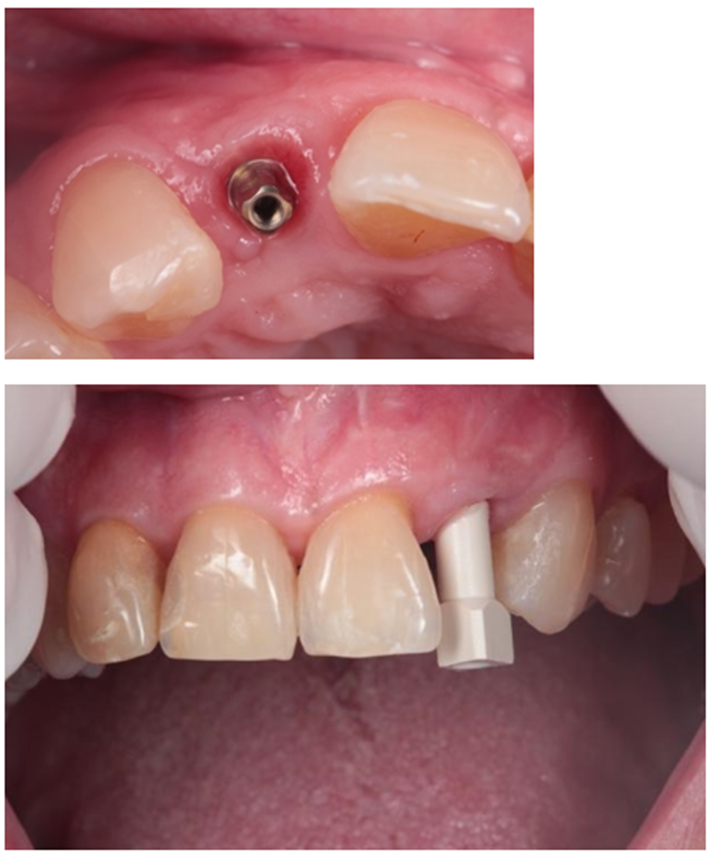

Após 8 meses da ROG, foi instalado um implante Cone Morse Due Cone 3,5 x 11mm através da técnica de cirurgia guiada por computador (Vídeo 2).

A escolha da técnica empregada justifica-se pela menor morbidade do procedimento cirúrgico e melhor acurácia no posicionamento do implante; conforme demonstrado por Nomiyama et al., 2022, ao utilizar o Sistema Implacil de instalação de implantes pela técnica guiada por computador. Imediatamente após a colocação do implante, foi instalada prótese provisória sem contato oclusal sobre pilar Ideale 3.3 x 4. Depois de quatro meses de pós-operatório, foi feito o escaneamento do componente protético utilizando transferente digital Exocad e a prótese em zircônia foi finalizada (Figuras 4 e 5).